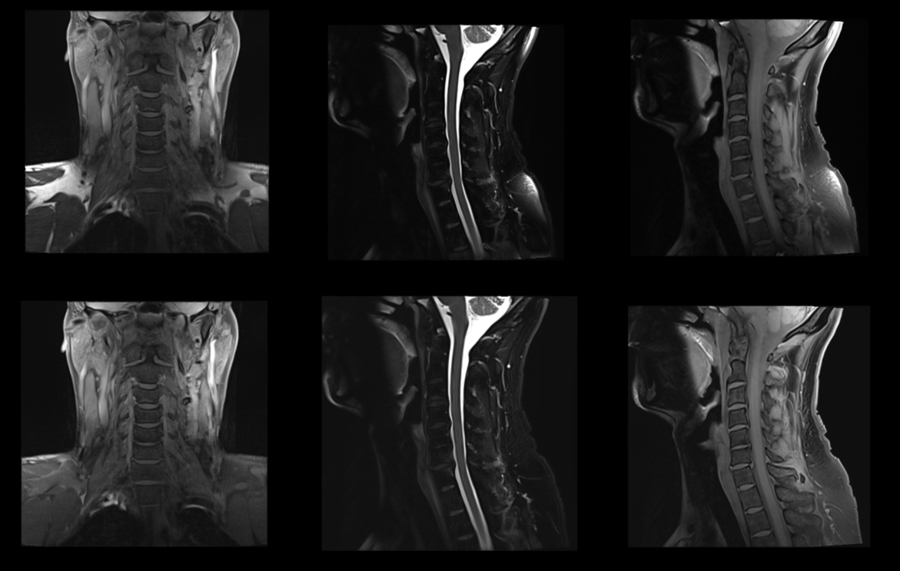

颈椎成像,使用CoilShim后,压脂不均匀区域的压脂效果明显改善。